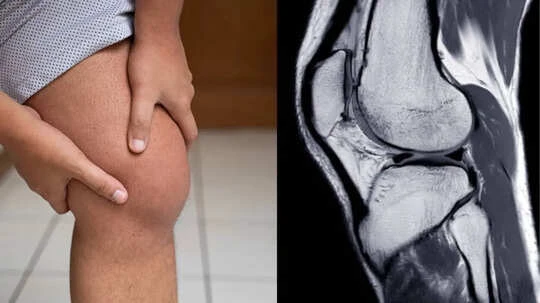

Also referred to as joint effusion or a “swollen knee,” this condition occurs when fluid builds up within the joint space, making the knee appear visibly enlarged and puffy. While it most commonly affects the knee, it can also occur in other joints like the ankle, elbow, or shoulder. Common knee effusion symptoms include:

- Imaging tests like X-rays or MRI scans

These tests help determine whether the swelling is due to injury, infection, or chronic disease. “In some cases, joint aspiration is performed, where fluid is removed from the knee and analysed to check for infection or crystal deposits. Blood tests may also be used to identify any underlying condition contributing to the effusion,” said Dr. Verma.